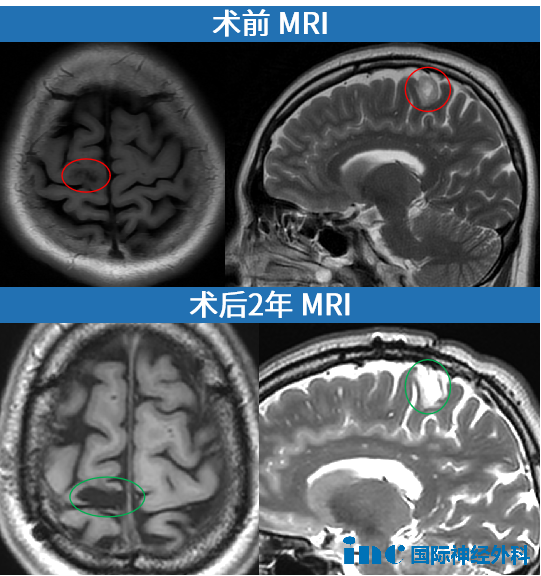

41岁女性患者莫女士分享其右额叶低级胶质瘤的完整诊疗经历。2022年11月3日,患者在办公室工作期间突发癫痫发作,出现明显抽搐症状及意识丧失,经紧急送医救治。后续医学检查确诊为右额叶低级胶质瘤,影像学显示肿瘤位置紧邻运动功能区,存在压迫重要脑组织导致运动功能缺损的潜在风险。

2022年12月4日,由巴特朗菲教授主刀在苏州实施肿瘤切除手术,手术全程持续3.5小时。术后患者意识状态恢复良好,四肢活动功能正常,术后第二天即从ICU转入普通病房。术后病理学检查证实肿瘤获得完全切除,周边脑组织结构和浅静脉系统完整保留。术后一个月随访显示,患者已恢复正常工作能力,并能顺利完成旅行活动。

长期随访结果与康复评估

术后一年随访检查显示肿瘤完全切除无残留病灶,癫痫临床症状未再发作。巴特朗菲教授建议将后续复查频率调整为每年一次平扫检查。术后两年随访评估确认无局部副作用等并发症,临床治疗效果显著,医疗团队建议每1.5年进行一次常规核磁共振检查。